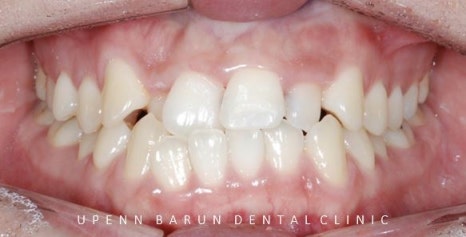

위, 아래 앞니가 정확히 맞물리지 않았던 이전과는 달리

입천장쪽으로 쏙 들어가 있던 위앞니가 제 자리를 찾으며

치아들이 가지런히 펴졌는데요 ^^

앞니의 높이와 모양이 불규칙하고

잇몸선이 삐뚤삐뚤해 치아의 잇몸 라인이 고르지 못했던 이전과는 달리

통증이 적은 레이저를 이용한 간단한 잇몸 성형을 통해 과도한 치은의 노출을 개선시켜 웃을때 가지런하며 시원한 느낌을 받을 수 있습니다 ^^

윗 앞니들의 아랫부분을 연결한 곡선이 아랫입술의 곡선과 평행을 이루어

예쁜 Smile Arc를 그립니다. 이것이 웃을때 더 예쁜 데이몬교정의 특징, Damon Smile 입니다.